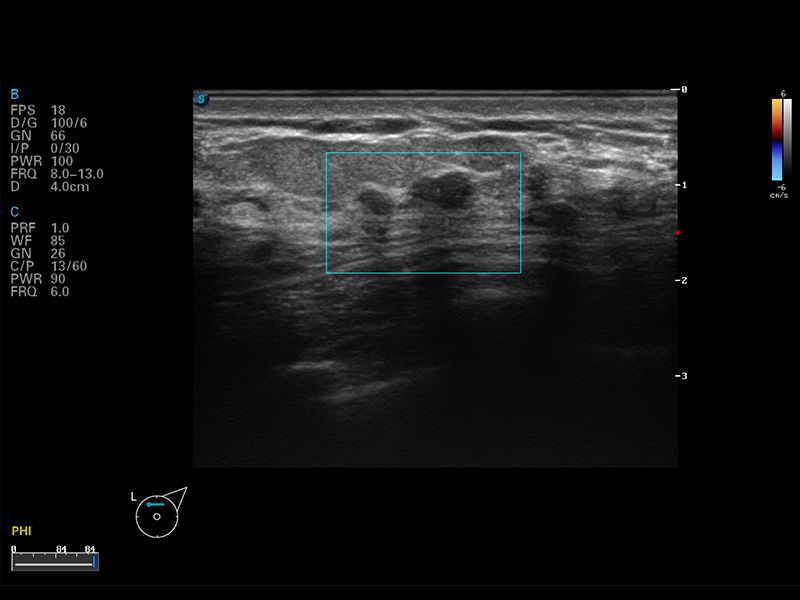

S8 EXP便携式彩色多普勒超声诊断仪是玖鼎集团研发的高端全身应用型便携彩超。高通道的VIS平台融合可视化(Visual)、智能化(Intelligent)和人性化(Smart)的特点,配以玖鼎集团自主研发生产的探头大家族,使您能够快速、准确的获得病人信息,提高工作效率的同时减轻疲劳。

μ-Scan微米成像

谐波成像

空间复合成像